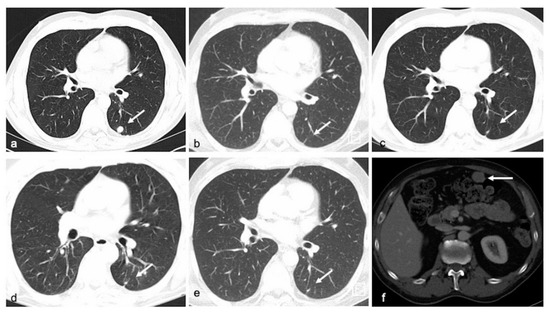

To assess radiological response towards therapeutic interventions, CT scans and, where indicated, MRI of the brain were used (as illustrated in Figure 7) and response was classified according to RECIST 1.1 criteria.

Figure 7.

CT scans showing the patient’s (ID 6) response to treatment with dabrafenib/trametinib (a) Axial CT images of lung demonstrate a secondary lesion (target lesion) in left lower lobe in baseline examination. Patient also has known osseous metastases (nontarget lesions). (b–d) 3, 6, and 9 months after therapy, there is still no evidence of the pulmonary nodule, the osseous metastases remain unchanged, in summary corresponding to partial response. (e,f) 13 months after therapy, there is still no evidence of the pulmonary nodule, but a new mesenteric implant was found, suggestive of progressive disease, which later was confirmed to represent metastatic tissue.